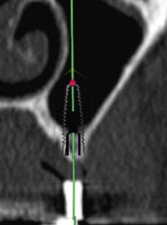

術前CT 2

第一大臼歯部

インプラントをシミュレーション